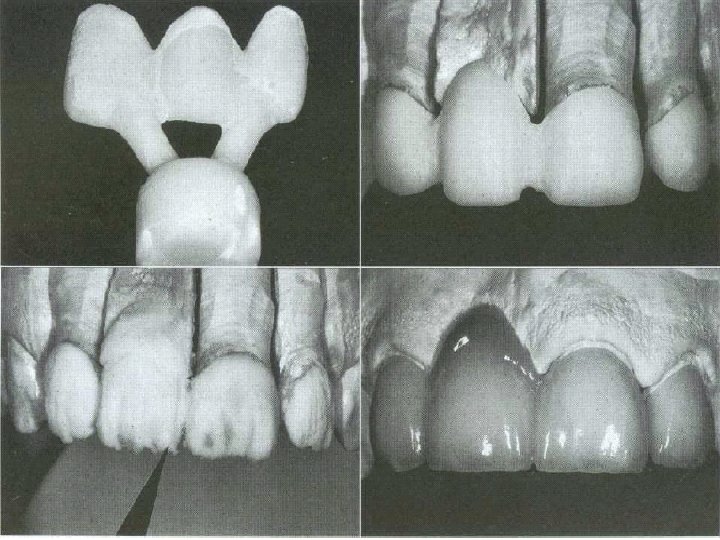

Fabrication Procedure

Body & incisal Porcelain application